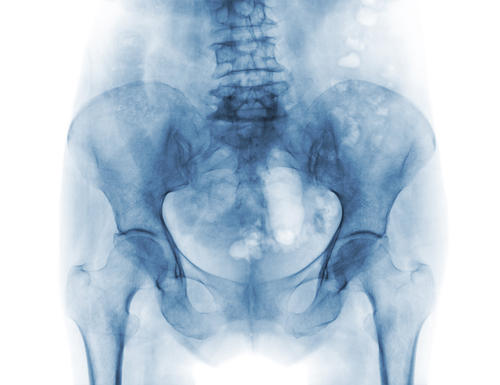

Полученные изображения рентгенолог анализирует сразу после рентгенографии. В описании он указывает состояние и структуру костей, крестцово-копчикового сустава, межпозвоночных дисков, позвонков, окружающих тканей. Доктор подробно описывает обнаруженные патологии и их параметры.

Посредством рентгена копчика становится возможным выявить травматические повреждения (вывих, перелом, ушиб), дегенеративно-дистрофические заболевания, деформации копчика, остеопороз, патологические процессы крестцово-копчикового сустава, гематому. Процедура информативна в плане визуализации остеохондроза, метастаз, аномалий развития, остеомиелита, новообразований злокачественного или доброкачественного генеза, воспалений, искривлений позвоночного столба.